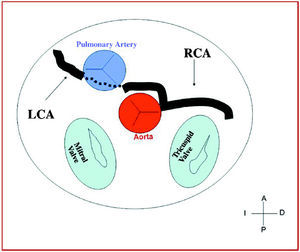

International groups are calling for registries including at least those anomalies that cause the majority of the clinical events (sudden death and myocardial ischemia) attributed to CAA,5-7 constituted by those originating in the contralateral or "wrong" sinus of Valsalva. This group includes single vessel coronary arteries ("hyperdominance" in the classification of Rigatelli et al4), since they have to supply blood to the myocardium arising from a single coronary ostium and establish routes that occasionally are similar to those of the CAA with origin in the wrong sinus of Valsalva (Figure 1).

Figure 1. Coronary arteriografía in left anterior oblique projection showing a single vessel right coronary artery.

3. Preaortic or interarterial (between the aorta and the pulmonary artery), in which the anomalous right coronary, left anterior descending or left main coronary artery cross the septum or the aortopulmonary space. This is the course that has most frequently been related to signs of ischemia and/or sudden death (Figures 7 and 8).

Figure 7. Diagram showing the interarterial course of a right coronary artery (RCA) originating in controlateral sinus.

Figure 8. Diagram showing the interarterial course of a left coronary artery (LCA) originating in controlateral sinus.